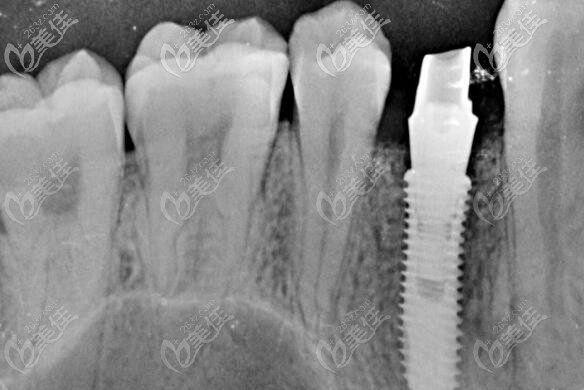

制定方案后,就帮顾客免费拍了口腔CT全景片,从CT片中可以看出来有单颗缺失,但是牙槽骨条件良好,无炎症,做种植也比较简单,性价比比较高的韩国登腾种植体就可以做。

天津雅尔美口腔的医生就利用数字化电脑进行了简单的设计,避开血管神经,确种植体的位置,以及种牙后的牢固性。确方案后就开始手术。